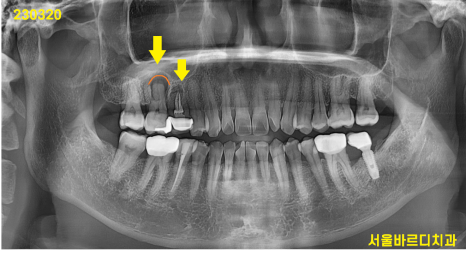

230320

구강 내에도 왕 뾰루지가 잡혔네요.

고름이 철철 흘러 나오는 상황

빨간색 화살표가 임플란트 보철입니다.

너무나 자연스럽죠~?

환자분들께서는 임플란트 해 넣은 치아인지

전혀 모르실꺼같아

표시 한번 해보았습니다.